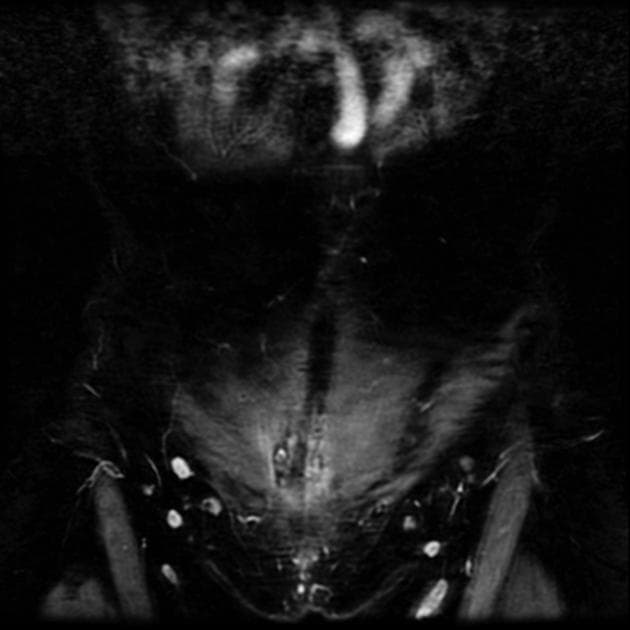

- Có một tổn thương dạng bất thường, nằm ở thành bụng trước, vị trí dưới rốn, liên quan đến sẹo mổ dọc theo đường mổ lấy thai trước đó (kích thước 19 x 15 x 11 mm).

- Tổn thương nằm ở phần sâu của lớp mô mỡ dưới da, sát bề mặt trước của cơ thẳng bụng (rectus abdominis).

- Tổn thương giảm âm (hypoechoic), không có vôi hóa hoặc thay đổi dạng nang.

- Tổn thương không nén dẹp được.

- Trên siêu âm Doppler, ghi nhận một vài tín hiệu lưu thông máu ở vùng ngoại vi của tổn thương.

- "Siêu âm cho thấy tổn thương giảm âm, không nén dẹp được, không vôi hóa hay biến đổi dạng nang; Doppler có thể thấy lưu thông máu ở vùng ngoại vi."